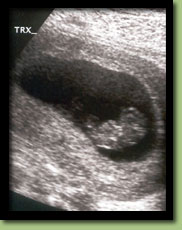

Oct. 23rd, Ultrasound @ 9 wks.

After a miscarriage at 9 weeks last December it was important to see that everything was okay. And as you can see, it was.